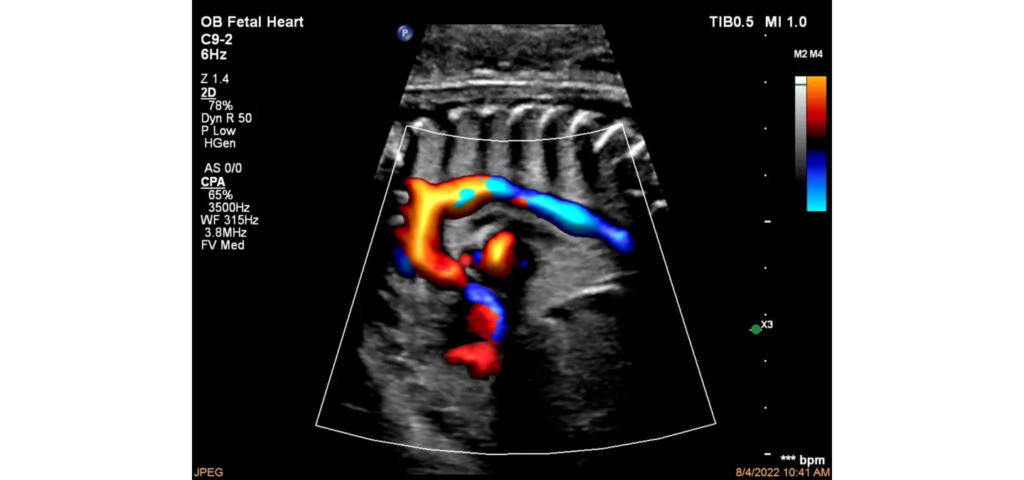

Philips EPIQ Elite ultrasound features an exceptional level of clinical performance, workflow, and advanced intelligence to meet the challenges of today’s most demanding practices. The EPIQ Elite platform brings ultimate solutions to ultrasound, with clinically tailored tools designed to elevate diagnostic confidence to new levels.